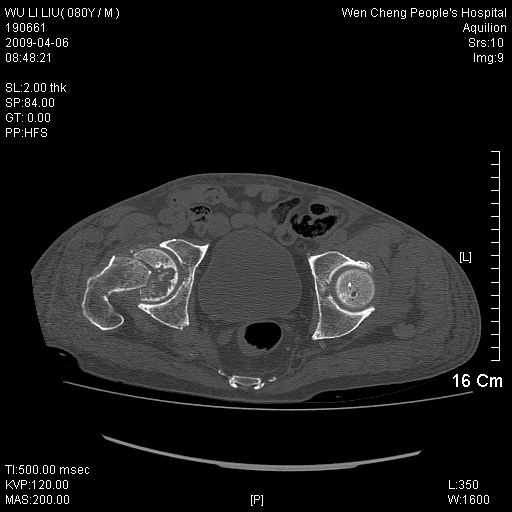

以下是引用zjzjr在2009-4-7 12:13:00的发言:[br]支持多发性转移瘤,右股骨颈骨折,腰椎亦有压缩性骨折.肝内胆管结石伴胆内外胆管扩张,左肾结石.

以下是引用liaoqiang在2009-4-7 8:44:00的发言:[br]考虑多发性骨髓瘤伴肝肺转移、肝内胆管结石、左肾结石、右股骨颈骨折。

以下是引用余辉在2009-4-7 8:52:00的发言:[br]椎骨及骨盆骨质疏松,骨破坏主要累及椎体,各骨破坏较广泛,各病灶边缘均较清晰锐利,血沉增快,白细胞增高.支持考虑多发骨髓瘤,建议查本尿周氏蛋白.[br]胆内胆管及左肾结石[br]右股骨颈骨折,考虑病理性